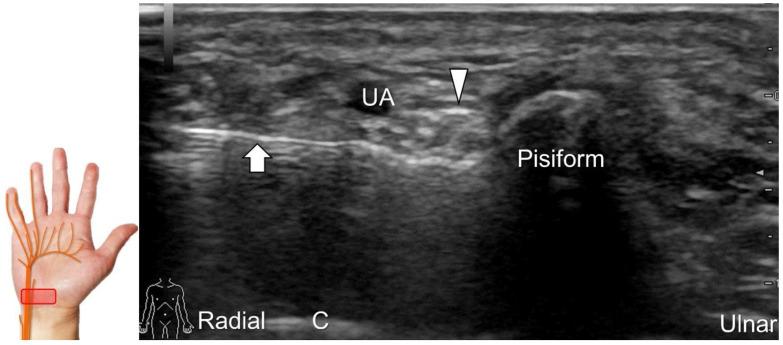

手腕/手部远端周围神经病变的超声成像与引导

超声已成为一种极具价值的工具,用于腕部区域周围神经病变的成像,特别是对于诸如腕管综合征和尺神经管综合征等常见病症。大量研究表明,神经在卡压部位近端肿胀、边界不清和平扁是神经卡压的特征。然而,关于腕部和手部的小神经或终末神经的信息却很匮乏。本文旨在通过全面概述这些神经卡压的扫描技术、病理学和引导注射方法来填补这一知识空白。本综述详细阐述了正中神经(主干、掌皮支和返支)、尺神经(主干、浅支、深支、掌尺皮支和背尺皮支)、桡浅神经、骨间后神经、掌总/指固有神经和背总/指固有神经。一系列超声图像用于详细说明这些技术。最后,超声检查结果补充了电诊断研究,有助于更好地理解整个临床情况,而超声引导下的干预措施对于治疗相关神经病变是安全有效的。